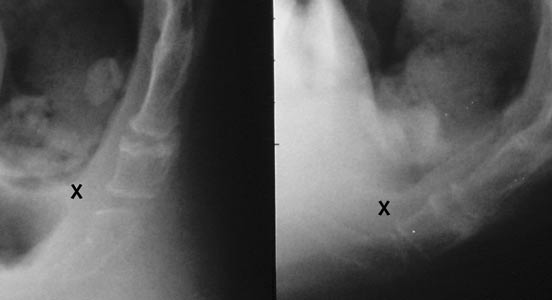

Case #5. The mobility is here around 30°. There is a narrowing of the joint space at its anterior aspect (X), but without friction. Note the irregular aspect of the sacrococcygeal joint, but without any motion, thus not a painful abnormality.

Case #6. This case is borderline. The mobility is just exceeding 25°, but the first mobile bone is eroded at its anterior part by the tip of the sacrum (X). Furthermore, the joint space was tender at palpation under fluoroscopic control, and the steroid injection was successful, establishing the responsibility of the joint.